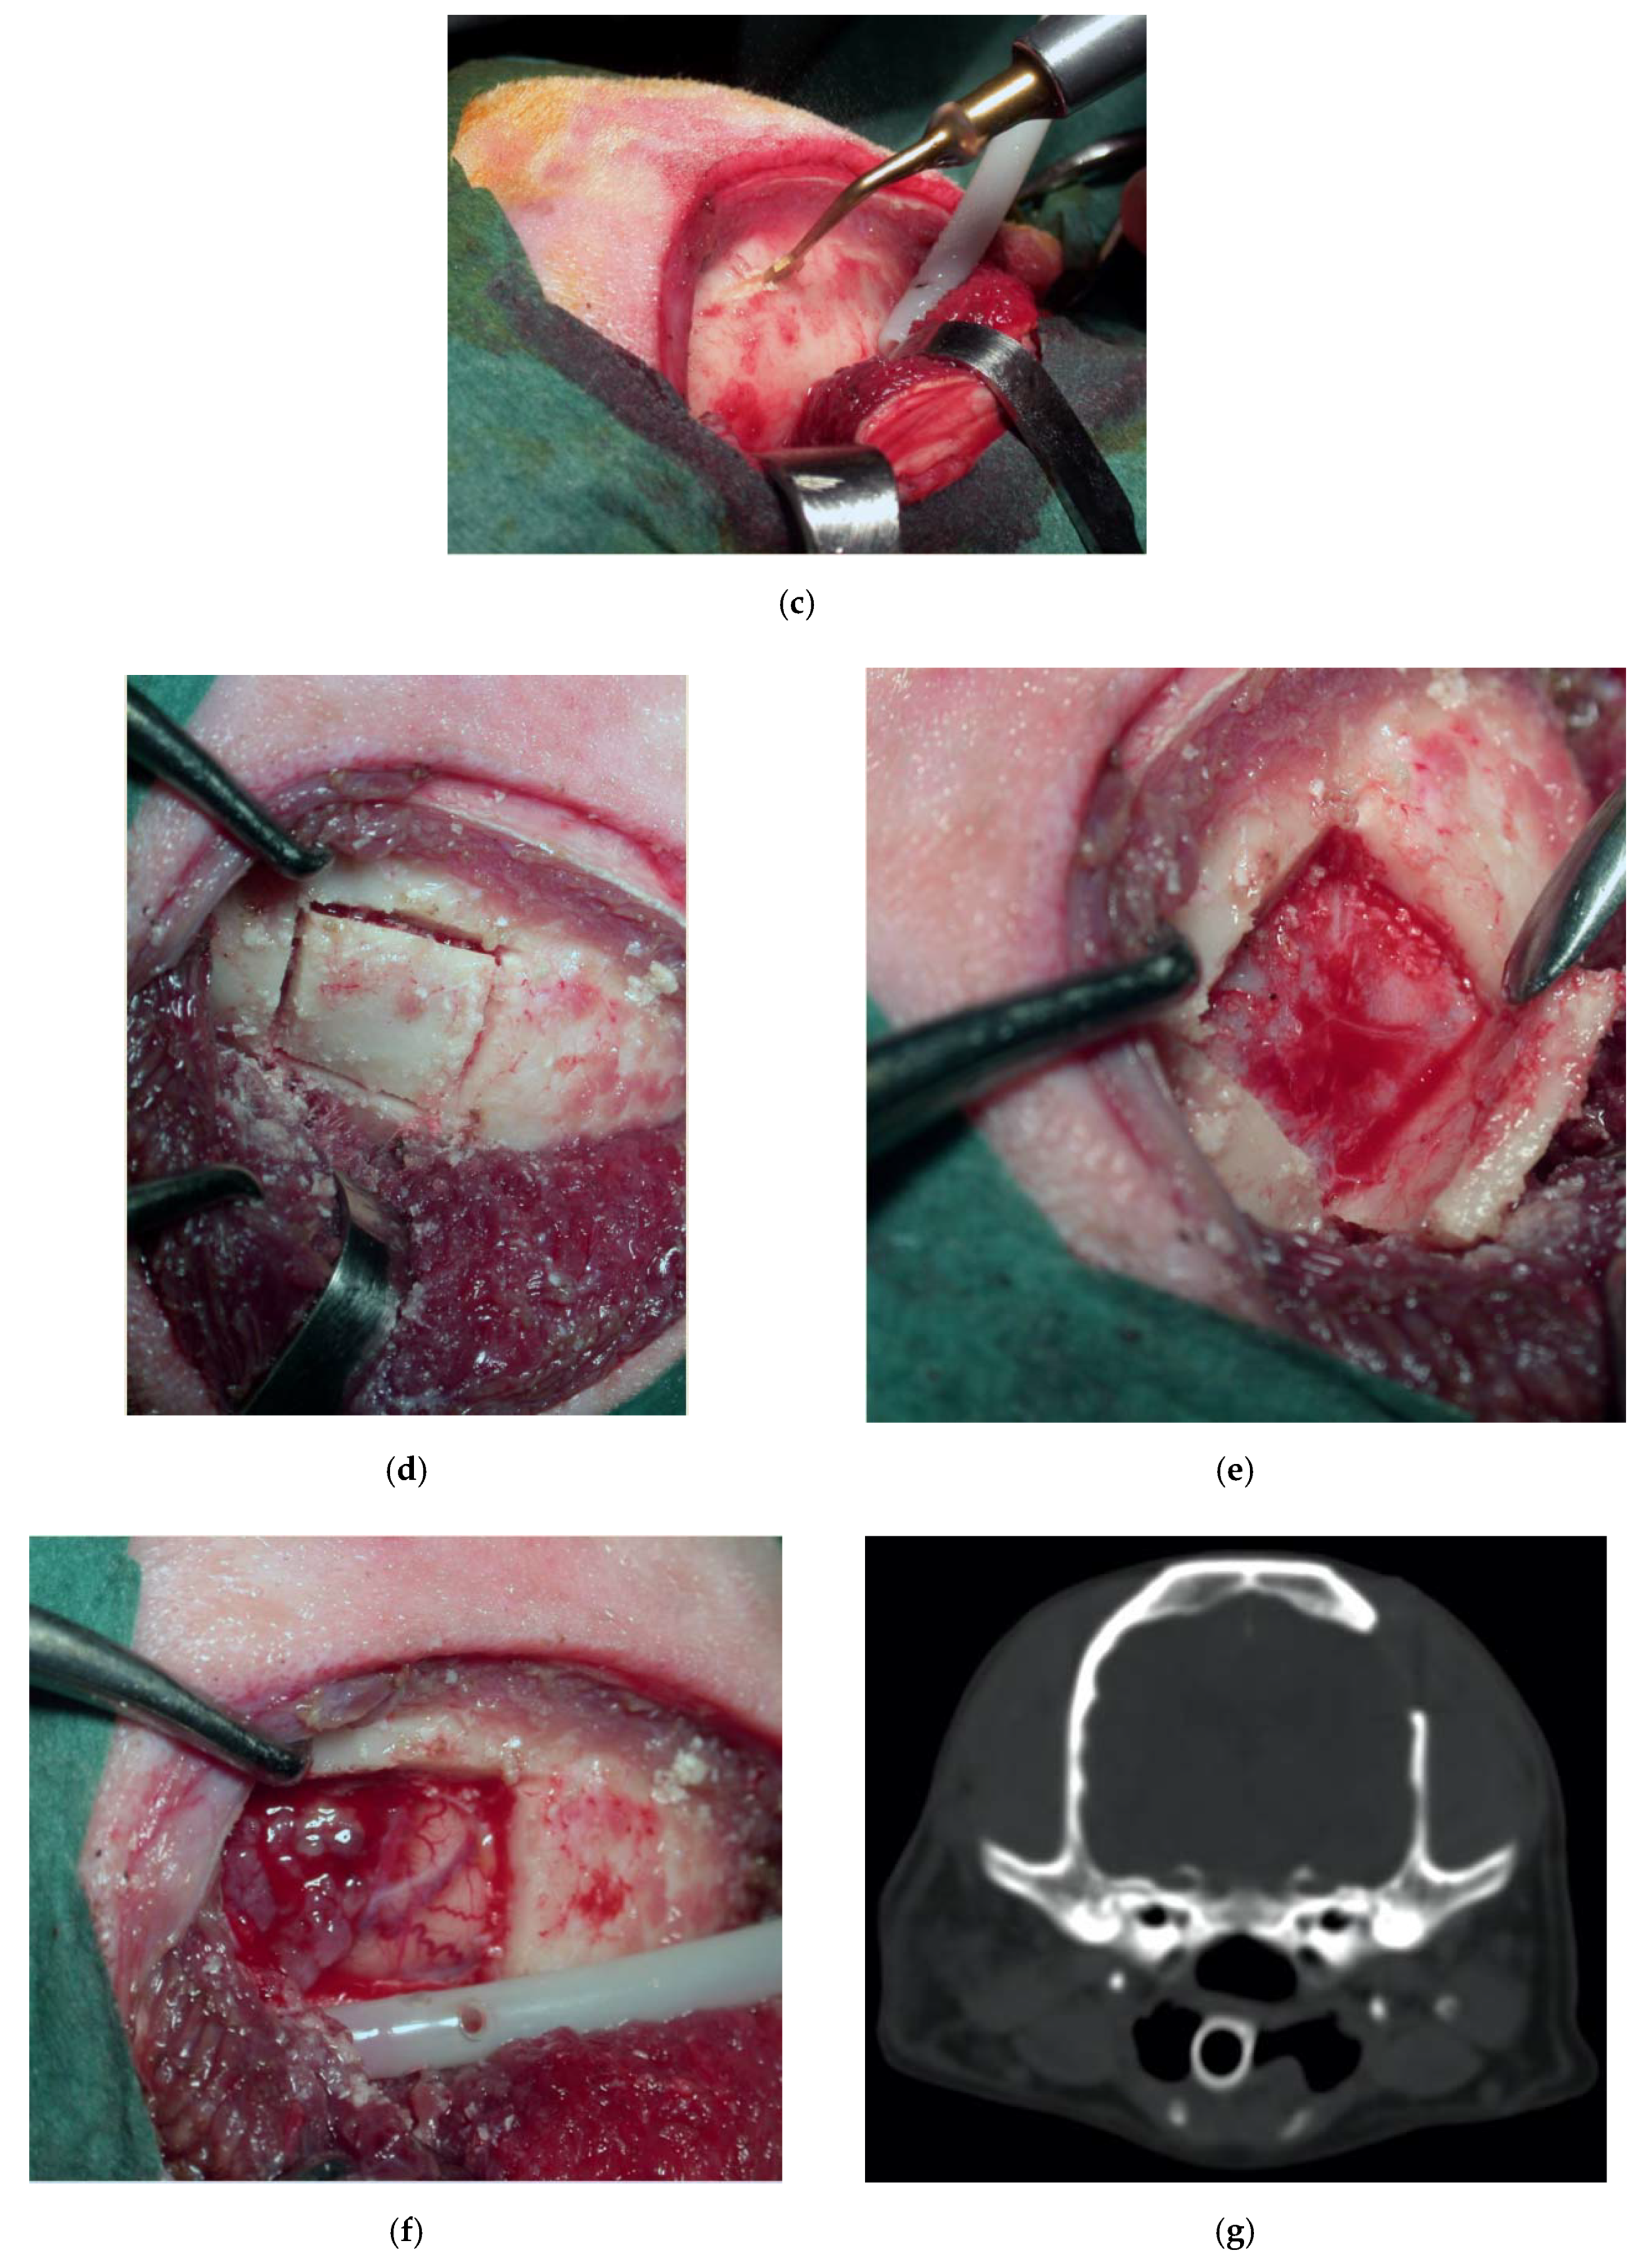

Dog, female, crossbreed, six years old, 14 kg, who suffered from seizures due to a suspected left intracranial parietal meningioma. She underwent a lateral rostro tentorial craniotomy with the piezoelectric bone scalpel. No dura mater sinus was present. The scalpel was essential in sparing the underling dura and brain. The tumor was completely removed, and recovery was complete, without complications (Figure 6).

Figure 6.

Preoperative contrast-enhanced CT scan, showing a suspected left parietal meningioma (a). Intraoperative pictures showing the initial steps of the craniotomy (b). The bone flap was cut with piezoelectric scalpel and an angled large saw tip (OT7, Osteotomy Tips Kit, Mectron Medical Technology, Genoa, Italy) (c,d). The dura was completely preserved (e). En bloc removal of meningioma (f). Postoperative CT scan performed at six-month follow-up, showing the sharpness of the edges of the craniotomy. No osteosclerosis or bony resorption was evident (g).